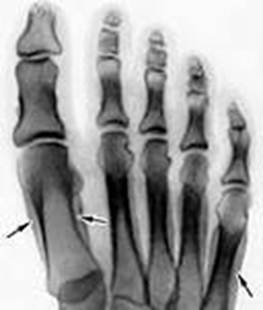

Наиболее часто периостозы перенапряжения наблюдаются на берцовой кости; рентгенологически выявляются периостальные наслоения.

Периоститы у спортсменов могут также явиться следствием многократных травмирующих надкостницу воздействий, обусловленных техникой спортивных движений. Они особенно легко формируются в тех участках ОДА, где отсутствует или мало выражен мышечный покров и недостаточен слой подкожной клетчатки. Такими участками являются передневнутренняя поверхность большеберцовой кости, наружная поверхность грудины, тыльная поверхность кисти и стопы и подошвенная поверхность пяточной кости.

Повторные ушибы передней поверхности голени происходят чаще всего при ударах о препятствие при барьерном беге, о гимнастические снаряды (перекладина, бревно и др.), в игровых видах спорта (футбол, гандбол, баскетбол и др). Ушибы грудины отмечаются в момент взятия грифа штанги на грудь и, реже, при гимнастических упражнениях на перекладине. Многократные ушибы тыльной поверхности кисти характерны для фехтования и бокса; ушибы пятки типичны при прыжках в длину, тройном прыжке.